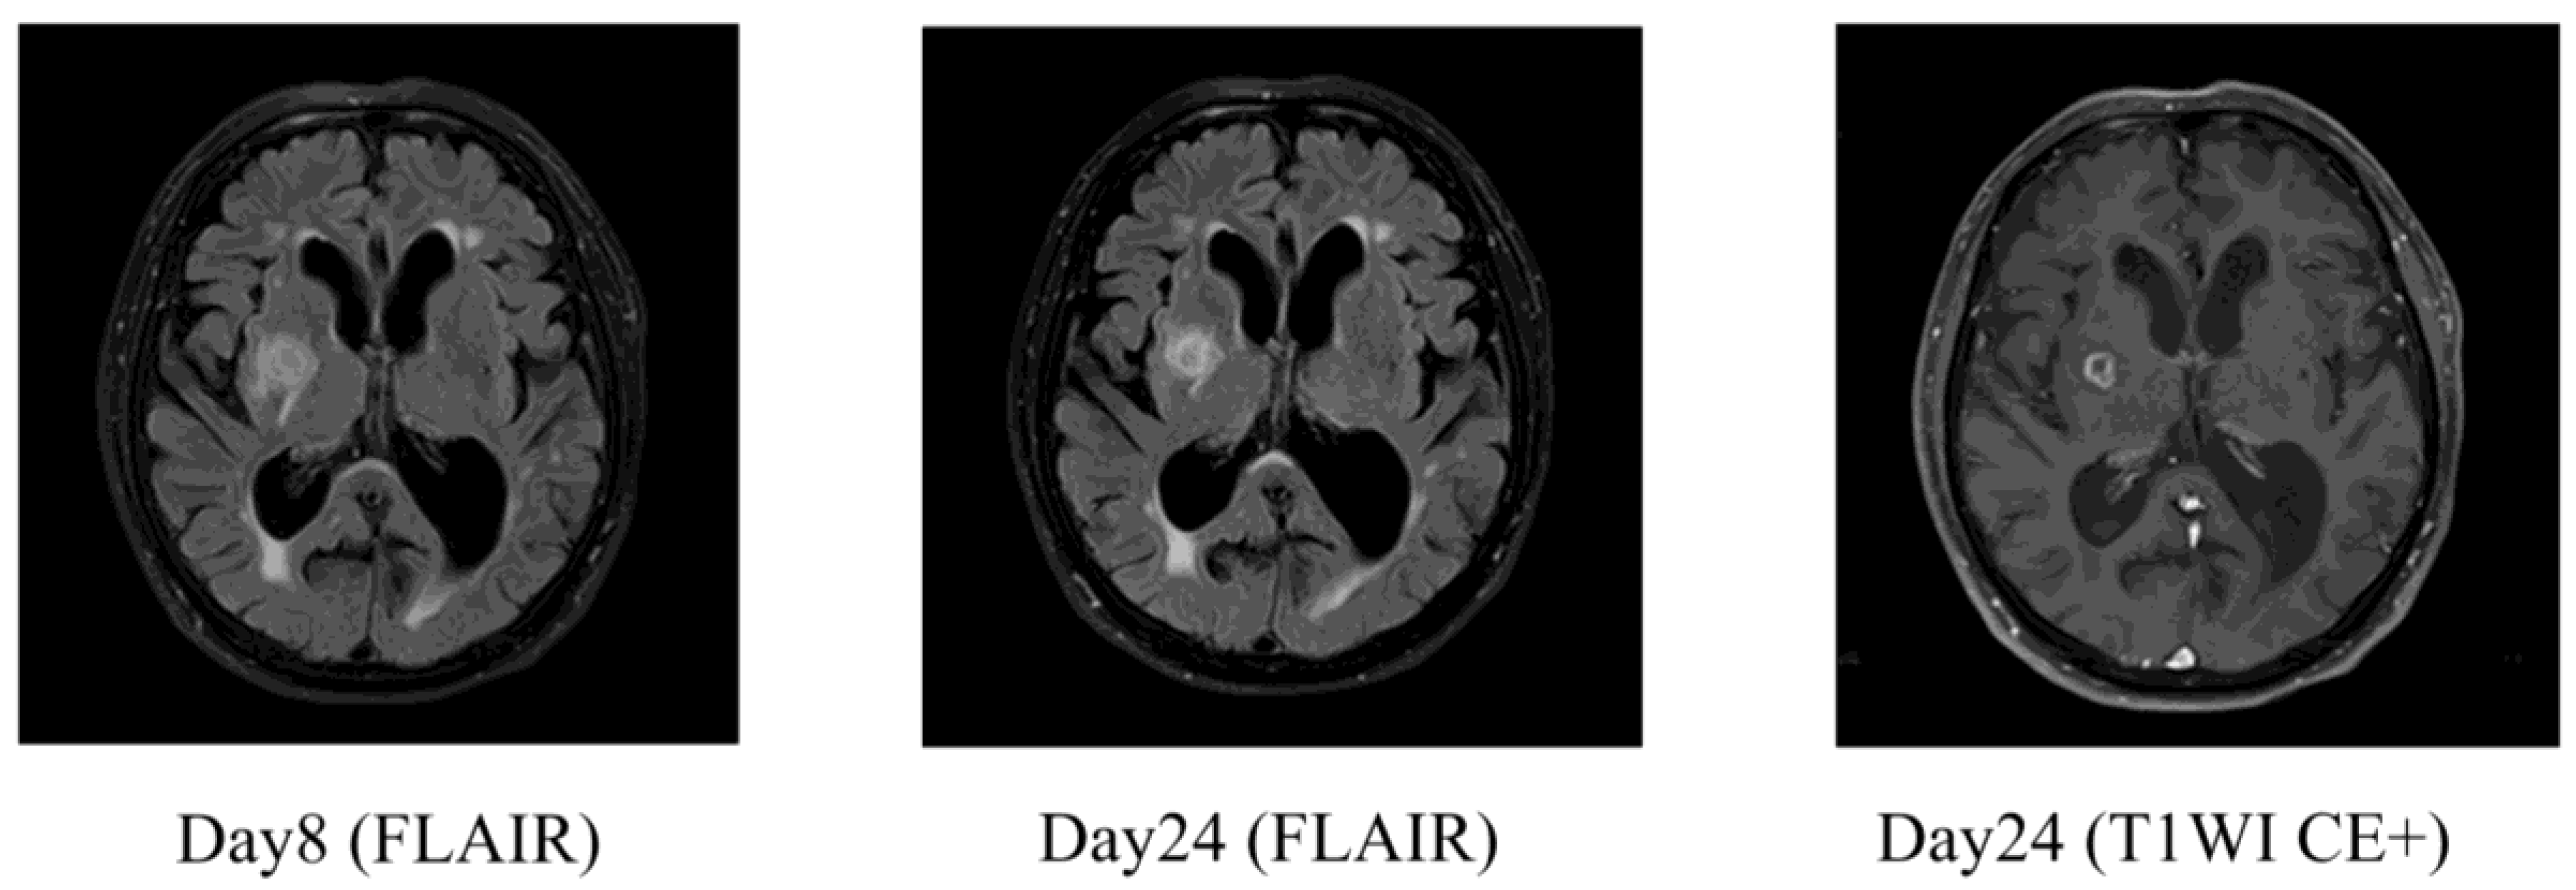

On day 3, the causative organism was identified to be Klebsiella pneumoniae. Abdominal contrast-enhanced CT and urinalysis revealed liver abscess, urinary tract infection, and bacteremia. Based on antimicrobial susceptibility testing, treatment was de-escalated to ceftriaxone. Whole-spine MRI revealed cervical spinal canal stenosis between the C3–C6 levels. On day 9, a tap test was performed, and lumbar puncture revealed an opening pressure of 6 cmH₂O. The CSF appeared clear with slight xanthochromism. A total drainage volume of 13 mL was achieved. Laboratory analysis revealed a glucose level of 115 mg/dL, protein concentration of 38 mg/dL, and white cell count of 2 cells/μL—findings which were inconsistent with meningitis. The absence of CSF pulsation and the low drainage volume raised the possibility of impaired CSF outflow because of cervical spinal canal stenosis and consequent communication disturbance. The patient’s gait disturbance improved significantly after the tap test was performed. Although his overall Mini-Mental State Examination (MMSE) score remained low, improvement was noted in the orientation component. Based on these findings, probable iNPH was diagnosed and a 12 mm brain abscess was incidentally found in the right basal ganglia (Figure 3-a).

By day 24, follow-up contrast-enhanced MRI confirmed encapsulation of the abscess (Figure 3-b). As the infection showed signs of improvement, a six-week course of ceftriaxone was planned before surgical intervention. On day 49, considering the possibility of impaired CSF circulation caused by cervical spinal canal stenosis and the presence of a right basal ganglia abscess, a left-sided ventriculoperitoneal (VP) shunt was placed. Postoperatively, the patient showed significant improvements in both his gait disturbance and cognitive function (Table 2). He soon regained ambulatory independence and was discharged.

Figure 3. Brain MRI in Case 1 demonstrating a basal ganglia abscess and its encapsulation. (a) Day 8 FLAIR image showed a 12 mm lesion in the right basal ganglia, suggesting a brain abscess. (b) Day 24 follow-up MRI revealed clear encapsulation of the abscess on FLAIR and contrast-enhanced T1-weighted imaging (T1WI CE+).